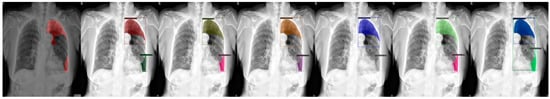

Figure 7.

From left to right: Ground Truth, ResNet50 (COCO), ResNet101 (COCO), ResNeXt101 (COCO), ResNet50 (LVIS), ResNet101 (LVIS), and ResNeXt101 (LVIS). This patient had pneumothorax in their left chest while having a fixation due to a probable accident.

We chose a few examples to demonstrate the capabilities of various models. These images consisted of X-ray images of pneumothorax patients with different areas of disease inflicted. The inclusion of multiple positions and areas in the figures lets us observe the possible outcomes and the differences between the models. In Figure 3 and Figure 6, the patients had pneumothorax on the right side of their chest, with the patient in Figure 6 only affecting the top part, while the patient in Figure 3 had pneumothorax on the outside wall of their right lung. In Figure 4, Figure 5 and Figure 7, the patients had pneumothorax in the left side of their chest, while the patients in Figure 4 and Figure 5 had the upper part of their left lung mostly collapsed, indicating a serious issue of pneumothorax disease. In Figure 5, there are cavity areas at the bottom part, too. In the same image, the ground truth included a portion protruding below the area of the top detection portion due to the late-stage pneumothorax with most of the upper part of the lung collapsing, and all models were unable to detect the cavity of the protruded part. In Figure 7, the patient is seen with a fixation, with the pneumothorax affecting the top left lung, albeit with a smaller area.